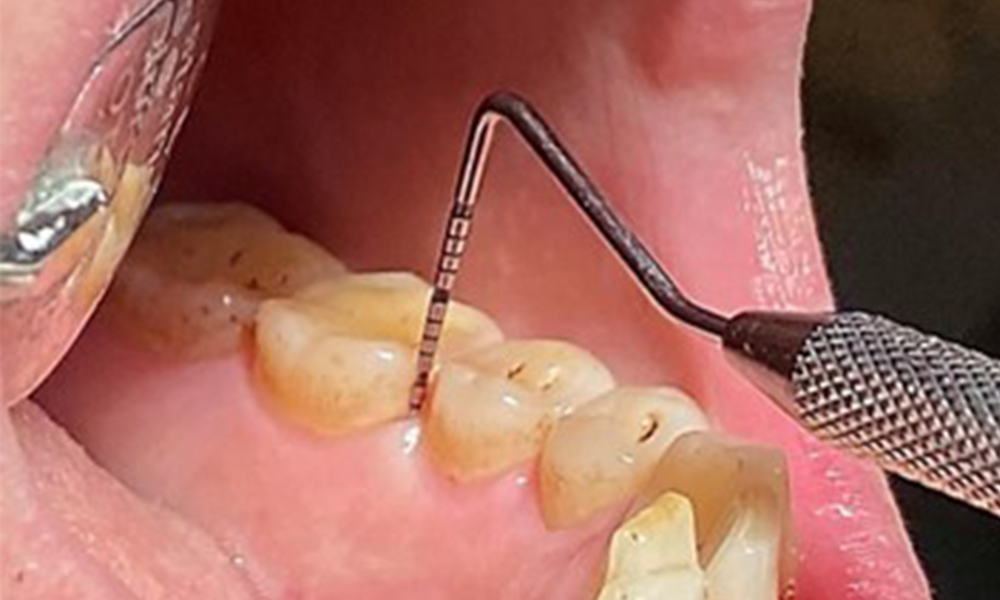

En raison d'un état de santé général par ailleurs favorable, les besoins déterminés lors de l'examen intra-oral seront déterminants pour le traitement. Il sera essentiel de déterminer périodiquement les profondeurs de sondage. Le saignement gingival diminue chez les fumeurs, c'est pourquoi le diagnostic clinique de la parodontite ne peut se faire que par sondage (Fig. 7). En se concentrant exclusivement sur la détermination des indices de saignement, on risque d'occulter une parodontite ou une gingivite existante. (5)

Sondage en poche (BOP) avec représentation de la dent 36 linguale

Fig. 7 Sondage en poche (BOP) avec représentation de la dent 36 linguale, © Dr R. Krapf

3. Il est important de documenter les résultats obtenus lors du rendez-vous thérapeutique. L'état du saignement au sondage (BOP), qui permet de mesurer la profondeur des poches parodontales aux premiers stades de la maladie, doit être déterminé lors de chaque rendez-vous. Cette mesure est particulièrement importante chez les fumeurs en raison de la diminution de la perfusion des tissus.